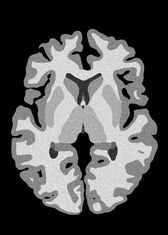

4.2 Registration to a 100 micron ex-vivo brain MRI volume

To showcase the efficacy of our method on real large scale images, we register a 250 in-vivo MRI image (Lüsebrink et al., 2017) to a 100 ex-vivo FLASH human brain volume (Edlow et al., 2019). This represents an inverse problem with more than 11.2B optimizable parameters (compared to 20M for clinical datasets), or 44.8GB of GPU memory. The entire problem does not fit on most GPUs, necessitating distributed multimodal registration. We optimize a composite transform - affine followed by a diffeomorphic mapping; details can be found in Section E.1. Multimodal deformable registration took 58 seconds on 8 NVIDIA A6000 GPUs, which is unprecedented at this resolution. Fig. 6 shows qualitative results, highlighting the ability to register highly detailed structures such as cerebellar white matter; these structures are not visible at macroscopic scales. The resultant advantages of performing registration at this scale can allow researchers to characterize the neuroanatomy at microscopic resolutions and allow morphometric analysis of cortical layers and subcortical nuclei among other structures.